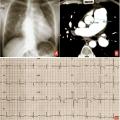

La radiographie de thorax retrouve le plus souvent une hypertrophie des artères pulmonaires associée à une cardiomégalie (augmentation de l’index cardiothoracique) (fig. 2A). La radiographie de thorax permet également de rechercher des éventuelles atteintes parenchymateuses associées orientant vers le groupe 3 (hypertension pulmonaire associée à une maladie respiratoire) ou de signes d’œdème pulmonaire orientant vers le groupe 2 (hypertension pulmonaire postcapillaire).

L’angioscanner thoracique permet également de mettre en évidence une hypertrophie des artères pulmonaires et des cavités droites (fig. 2B). Il est plus sensible que la radiographie de thorax pour rechercher des anomalies parenchymateuses associées ou des signes évocateurs de maladie veino-occlusive. Il a également un rôle important dans le bilan des hypertensions pulmonaires post-emboliques.

L’électrocardiogramme retrouve classiquement des signes d’hyper­trophie auriculaire et ventriculaire droite (fig. 2C).